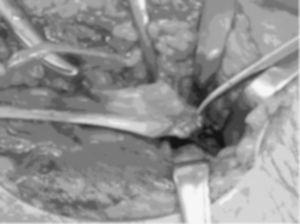

Se realiza una incisión curvilÃnea en la cara anterior del codo. Se continúa con una disección cuidadosa por planos, llegando a la aponeurosis profunda que se corta longitudinalmente para localizar el tendón distal del bÃceps que habitualmente se retrae unos 5 o 6 centÃmetros por encima del codo (fig. 3). Mientras se hace esta disección hay que proteger el nervio cutáneo externo del antebrazo. Se localiza la tuberosidad bicipital del radio para la reinserción del tendón. Las reinserciones y suturas se realizaron en diez casos (76,9%) con reanclaje mediante arpones (fig. 4), en dos casos con túneles óseos (15,4%), y en uno mediante un anclaje con técnica endobutton (7,7%). Los arpones utilizados fueron de distintas casas comerciales, pero siempre roscados y de 3,5 milÃmetros de grosor (fig. 5). En 5 roturas (50%) se utilizó un único arpón (fig. 4), 4 lesiones (40%) se reanclaron con 2 arpones y 1 (10%) con 3 (fig. 5).

Figura 3. Visión intraoperatoria que muestra la rotura del tendón distal del bÃceps (abordaje anterior).

Figura 4. Colocación de un arpón durante la intervención.